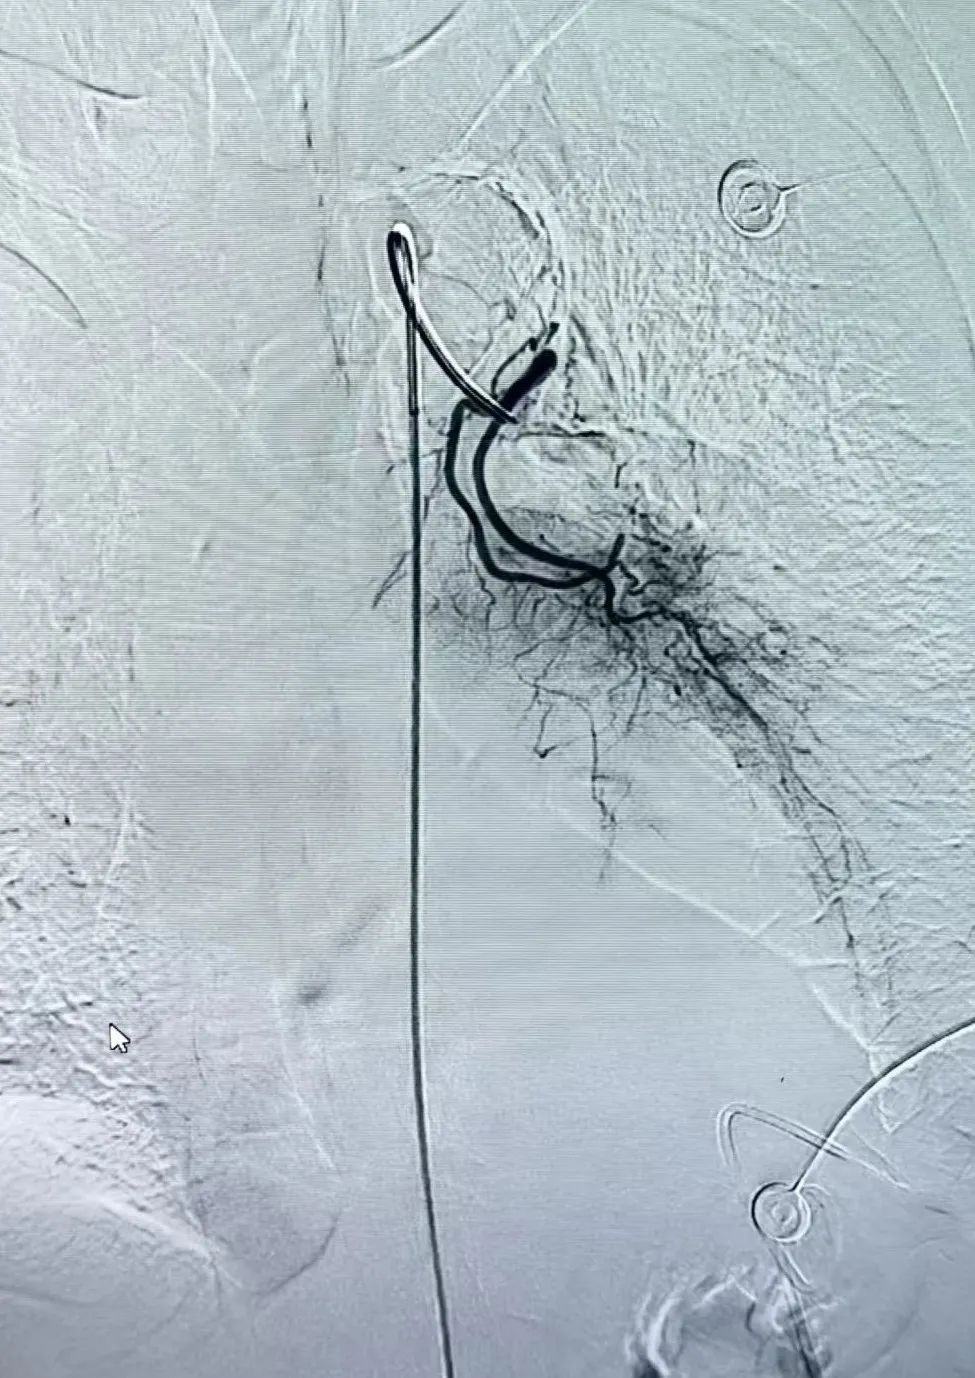

近日,宽城县医院肿瘤科团队完成首例支气管动脉化疗栓塞术(BACE),为74岁肺癌患者提供精准治疗。这一突破标志着医院在肿瘤微创介入领域取得进展,也为晚期肺癌患者带来新希望。

患者王大爷确诊肺恶性肿瘤3月,因无法耐受传统放化疗副作用,治疗效果受限。今年7月复查显示肿瘤增大,伴肺不张、胸腔积液,呼吸功能受损。医院肿瘤科介入团队经多学科会诊评估,在为患者实施胸腔积液置管术的同时,决定采用支气管动脉化疗栓塞术。

手术顺利,仅留微小穿刺创口,凸显微创优势,患者及家属十分满意。